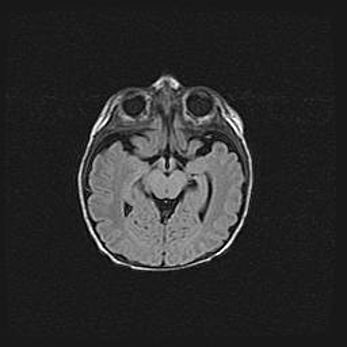

Наружная гидроцефалия с возможной атрофией височных областей.

Возраст: 28 дней

Вес: 3670 г

Пол: мужской

Окружность головы: 38 см

Срок гестации: 40 недель

Гидроцефалия головного мозга у новорожденных – это заболевание, которое характеризуется скоплением избыточного количества спинномозговой жидкости в желудочковой системе головного мозга в результате затруднения её перемещения от места выработки к месту поглощения в кровеносную систему или вследствие нарушения абсорбции. При открытой наружной форме гидроцефалии у новорожденных расширяются и переполняются субарахноидные пространства.

При нормотензивных  формах,  которые,  как  правило,  являются  следствием  перенесенных ишемических  повреждений  паренхимы  мозга,  возможно  сочетание микроцефалии  с нормотензивной гидроцефалией. В основе данных изменений лежит атрофия больших полушарий с преимущественной  локализацией  в  лобно-височных  областях.